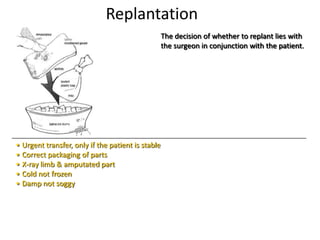

- Conditions that require emergency referral are discussed, such as bleeding, amputation, replantation, compartment syndrome, infections, and high pressure injection injuries. Proper management of these conditions focuses on rapid assessment and treatment to prevent further tissue damage.